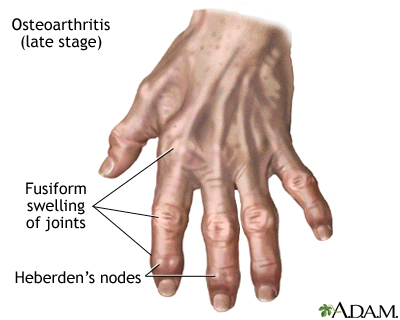

- Joint movement that causes a crackling (grating) sound, called crepitation

- Joint swelling (either due to fluid in the joint or the bones around the joints feeling larger than normal)

- Limited range of motion

- Tenderness when the joint is pressed